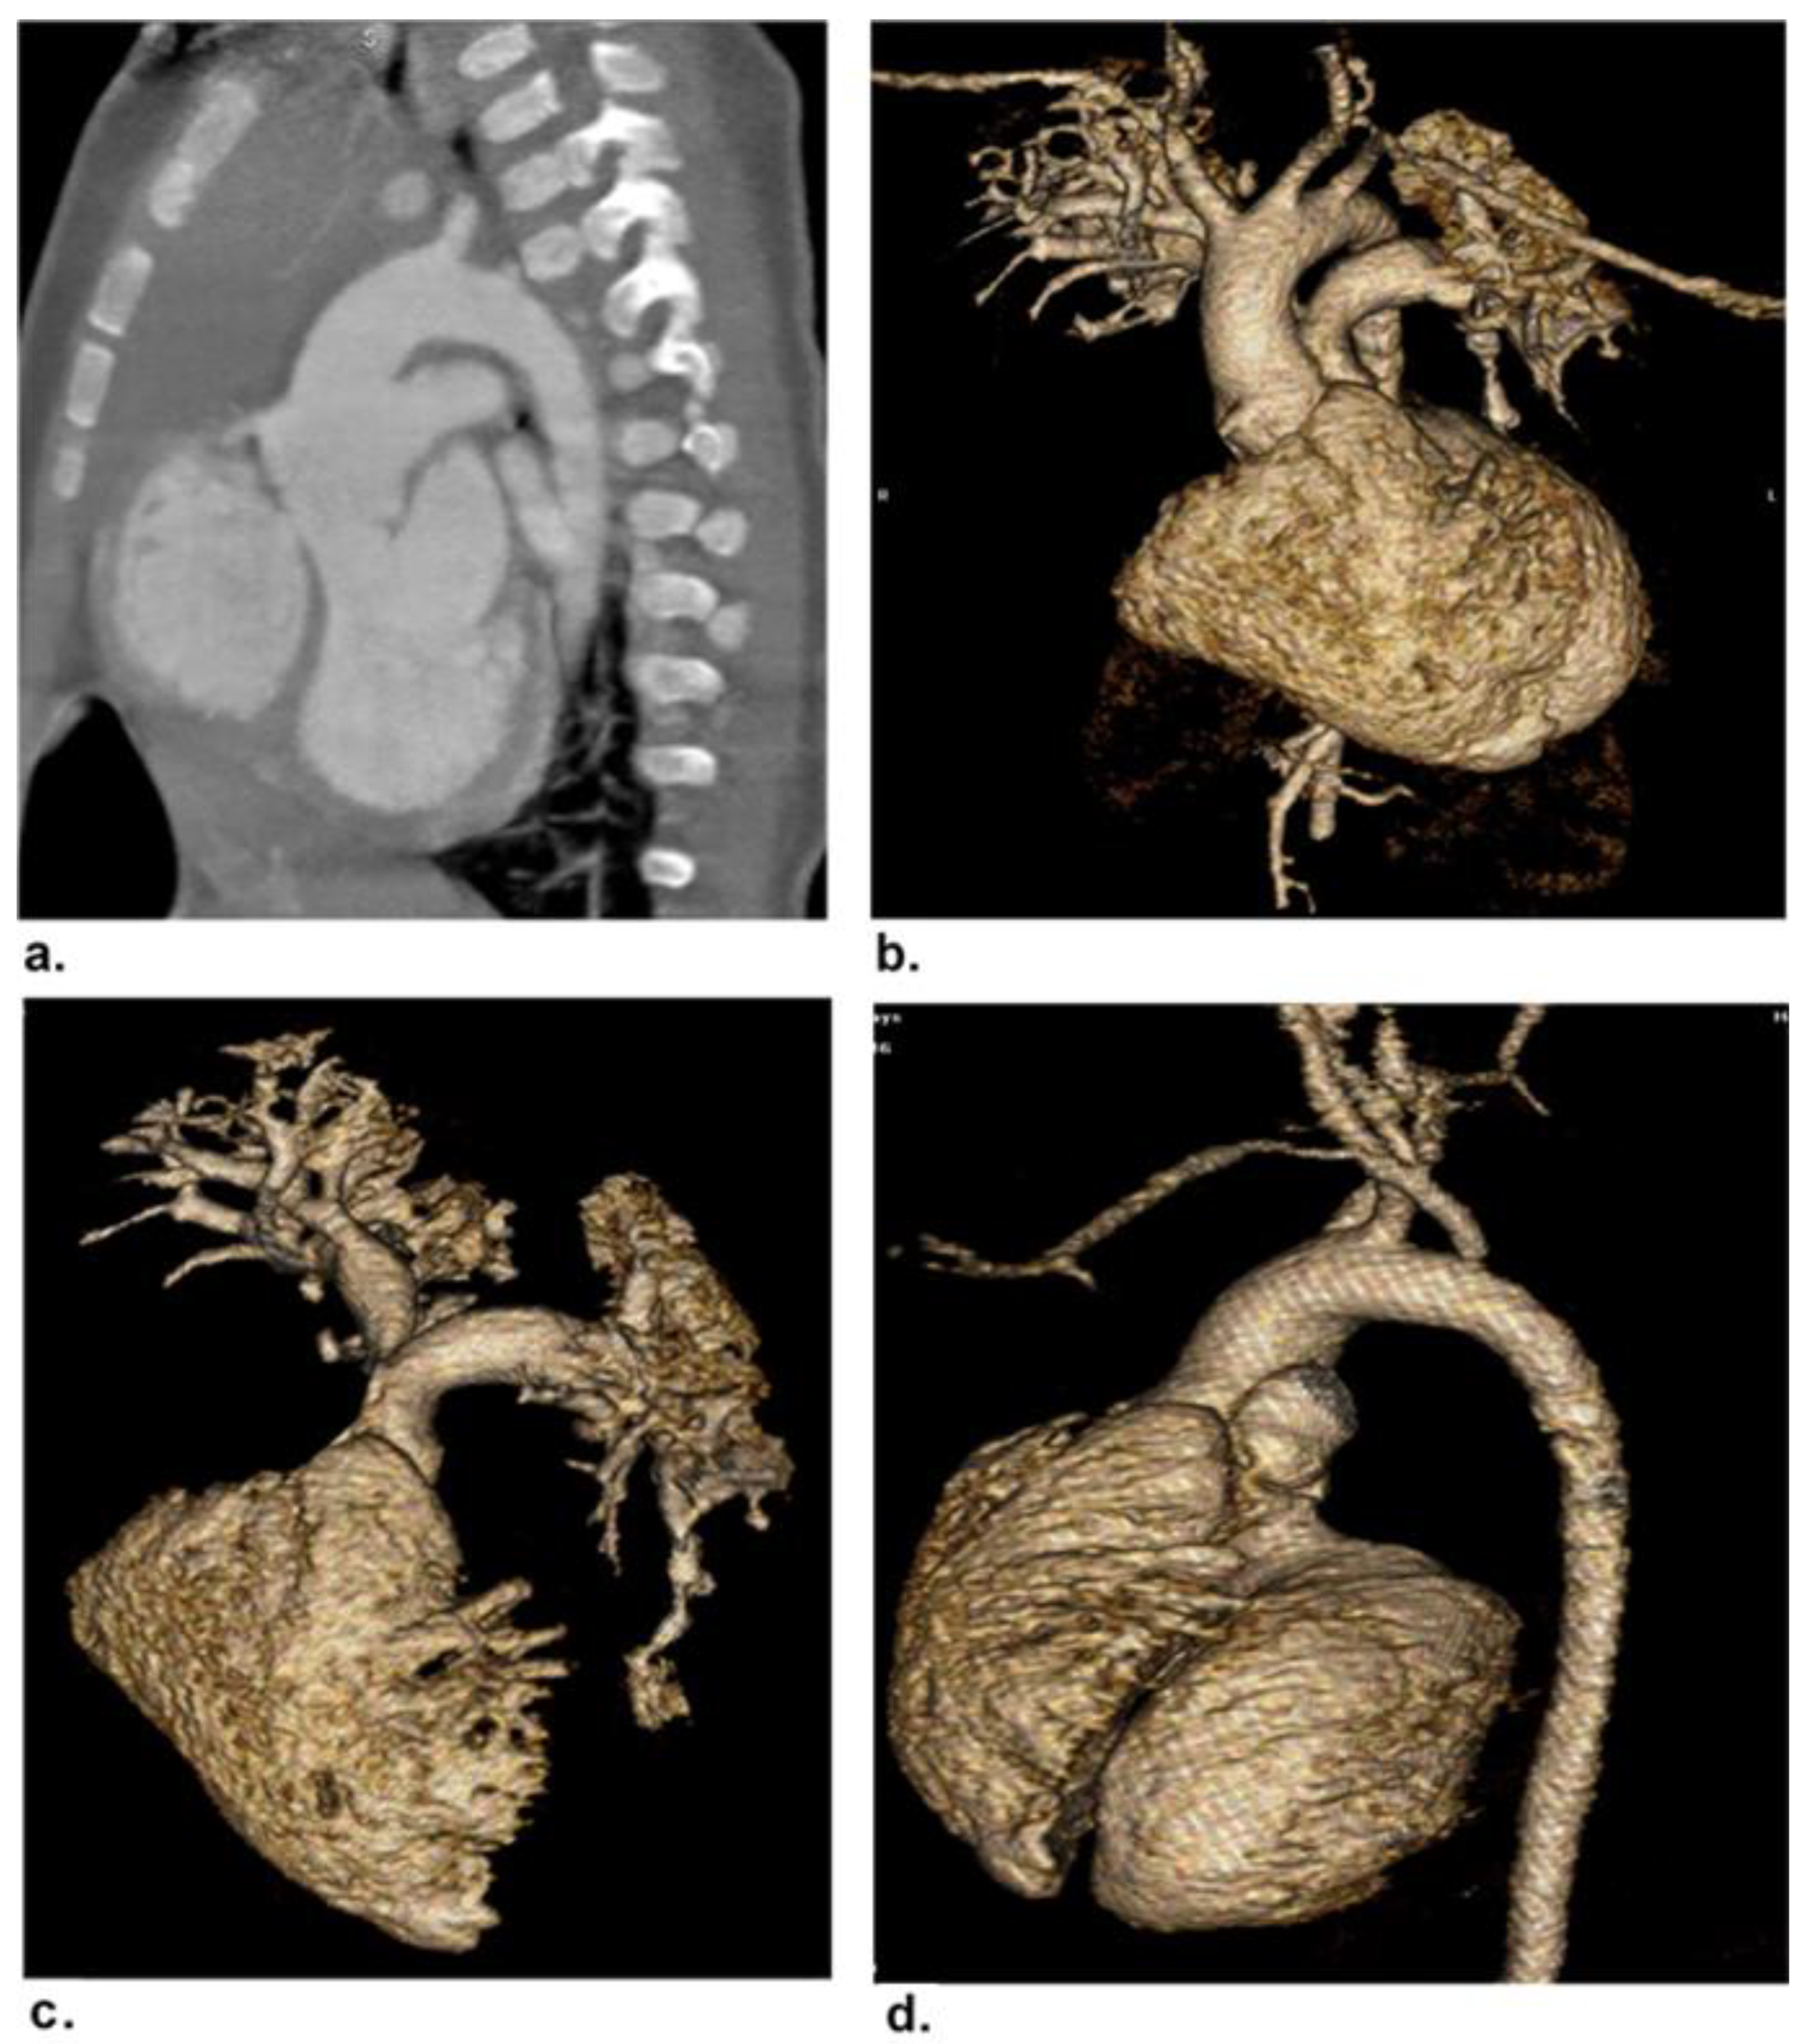

2.4. Image Post-Processing and Interpretation

3.5. Image Quality Evaluation